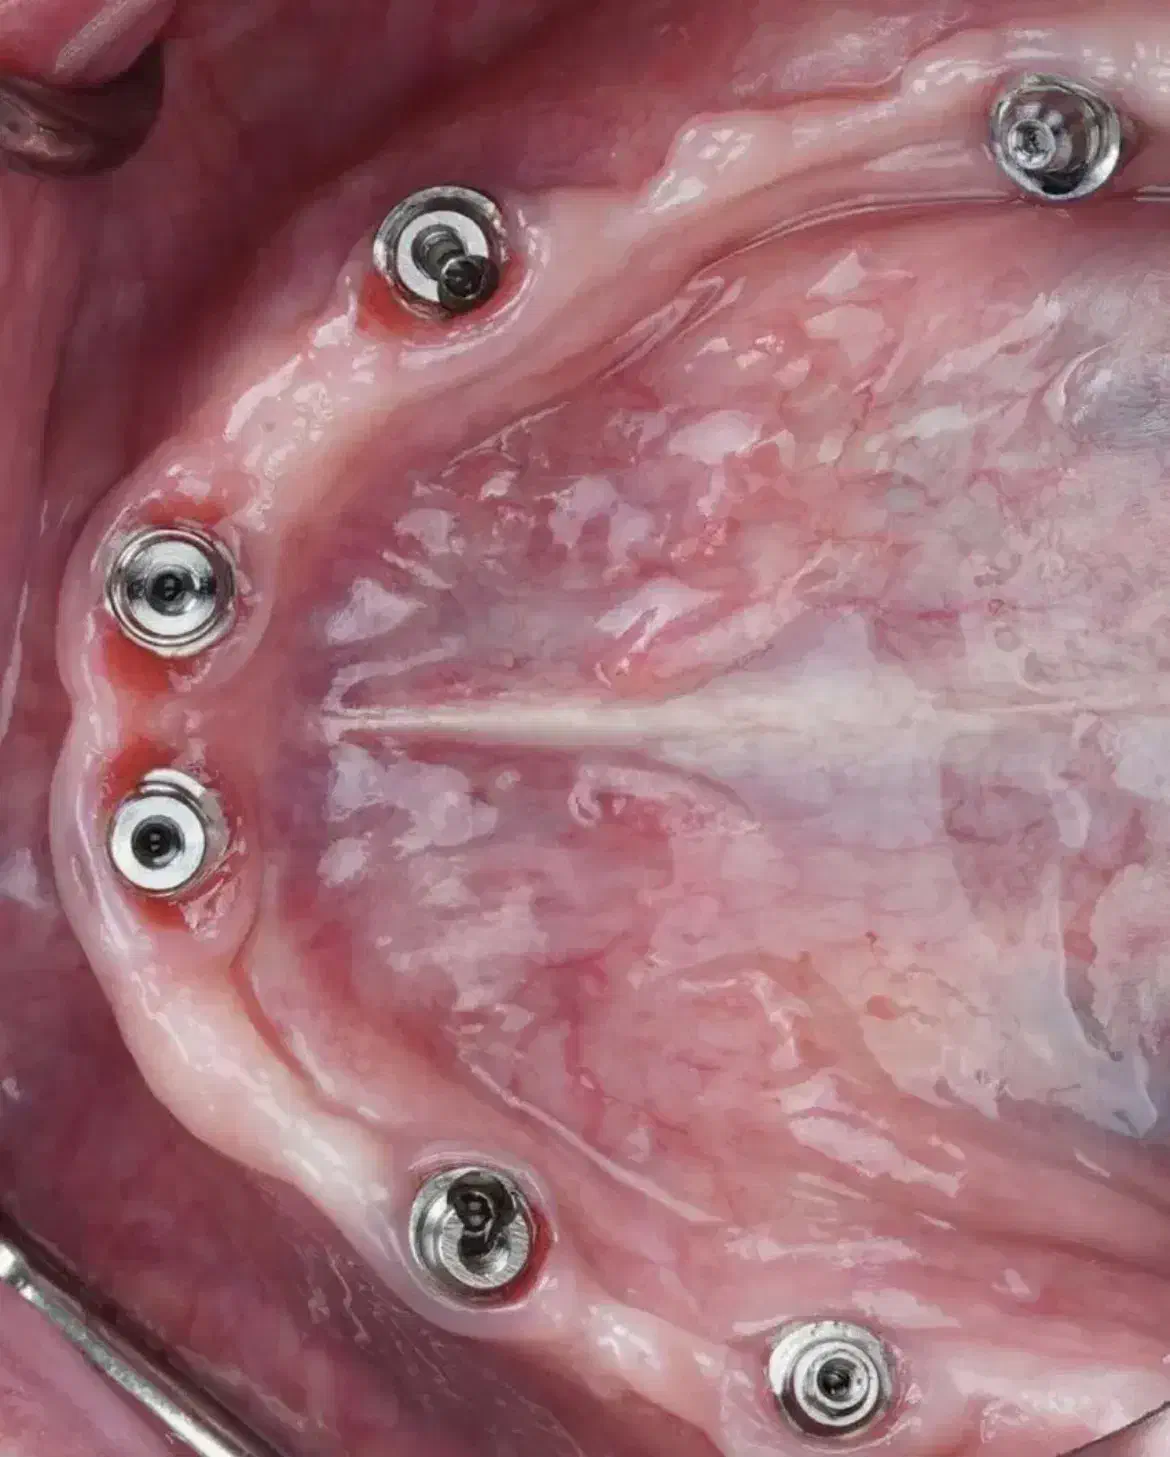

⚜️مطب دندانپزشکی ما، با بهرهگیری از دانش روز و تکنولوژیهای پیشرفته ، خدمات تخصصی دندانپزشکی و ایمپلنت را با بالاترین استانداردهای کیفی ارائه میدهد خدمات و امکانات ویژه: ویزیت و مشاوره اولیه رایگان شرایط پرداخت اقساطی بلند مدت فضای پارک اختصاصی و دسترسی آسان محیطی کاملاً بهداشتی و استریل جراحی ایمپلنت با حداقل تهاجم : استفاده از تکنیکهای جراحی پیشرفته برای کاهش درد، تورم و خونریزی بعد از عمل و تسریع دوره نقاهت بازسازی استخوان :استفاده از تکنیکهای پیشرفته بازسازی استخوان برای افزایش حجم استخوان فک و ایجاد شرایط مناسب برای قرارگیری ایمپلنت در بیمارانی که دچار تحلیل استخوان شدهاند ✅در مورد شرایط پرداخت اصلا نگران هزینه هاتون نباشید باهر توان مالی که باشید باهاتون راه میایم جهت کسب اطلاعات بیشتر و تعیین وقت مشاوره تماس بگیرید یا فامیلی و شماره تماس خودتون رو از چت دیوار برامون بفرستید باهاتون تماس میگیریم